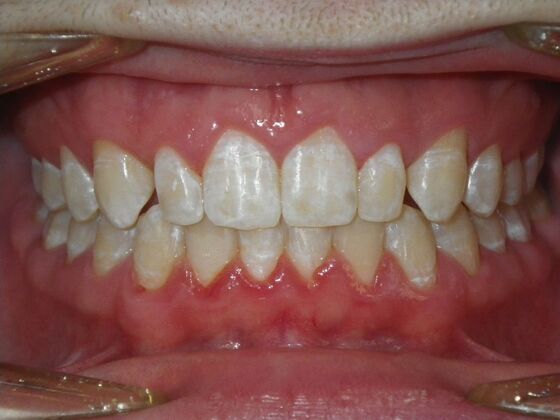

This patient does not like his anterior deep bite and the flaring of the right lateral incisor as well as anterior spacing. The solution was to correct his Class II molar relationship, Division II and deep anterior bite and close spacing as much as possible with addition of composite restorations on distals of lateral incisors. We began with utility archwires, eventually correcting Class II molar with distalizing appliance, and continued with final tip and torque. All that is left now is to ad composite to distals of upper lateral incisors.